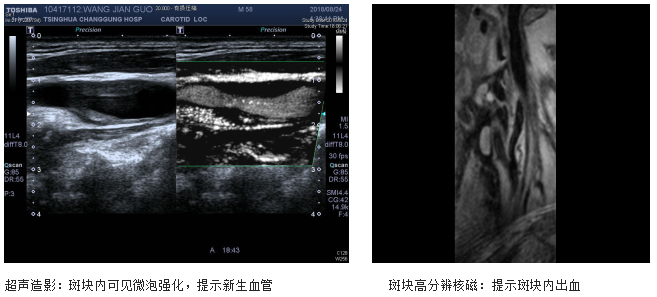

如果斑块增大到一定程度,就要及时行斑块稳定性评估,如果超声造影提示:斑块内有大量新生血管形成,斑块纤维帽不完整;斑块高分辨核磁分析提示:斑块内出血及存在大的脂类核心、纤维帽破裂等情况,说明斑块极不稳定,脱落导致远端脑梗塞风险较大。

术前斑块的影像学评估